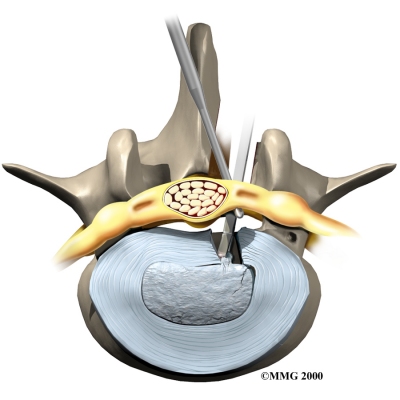

Discectomy

Discectomy

Surgery to take out part or all of a problem disc in the low back is called discectomy. Discectomy is done when the degenerated disc has ruptured (herniated) into the spinal canal, putting pressure on the spinal nerves. Surgeons commonly perform this operation through an incision in the low back. Before the disc material can be removed, the surgeon must first remove part of the lamina. Generally, only a small piece of the lamina is chipped away to expose the problem disc. This is called laminotomy. It usually creates enough room for the surgeon to remove the disc. If more room is needed, the surgeon may need to take out a larger section of the lamina by doing a laminectomy (described above).

Many surgeons now do minimally invasive surgeries that require only small incisions in the low back. These procedures are used to remove damaged portions of the problem disc. Advocates believe that this type of surgery is easier to perform. They also believe it prevents scarring around the nerves and joints and helps patients recover more quickly. Minimally invasive surgeries include percutaneous lumbar discectomy, laser discectomy, and microdiscectomy.